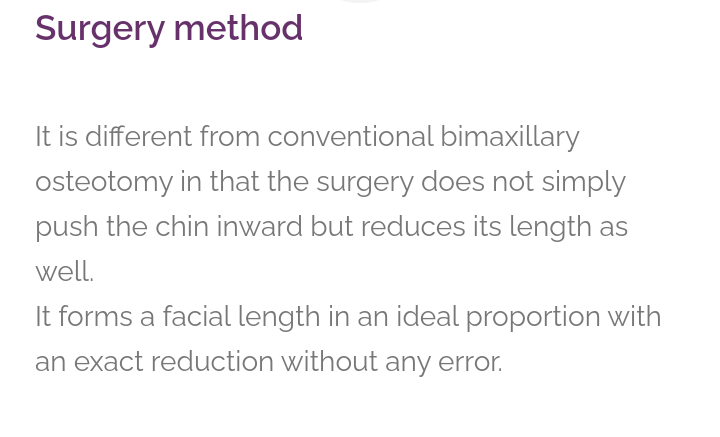

But how its possible to cut centre of maxilla?

Its because of stuff they use to perform surgery

Ultrasonic bone scalpel is great because only affect bone tissues. Make it safer.

02 exacly cause of long midface

How the surgery look?

Shorter nose and Reversed most of the downward growth

And that all possible due to unique scalpel and technique.

But how its possible to cut centre of maxilla?

Its because of stuff they use to perform surgery

Ultrasonic bone scalpel is great because only affect bone tissues. Make it safer.

They show many details

02 exacly cause of long midface

How the surgery look?

Shorter nose and Reversed most of the downward growth

And that all possible due to unique scalpel and technique.